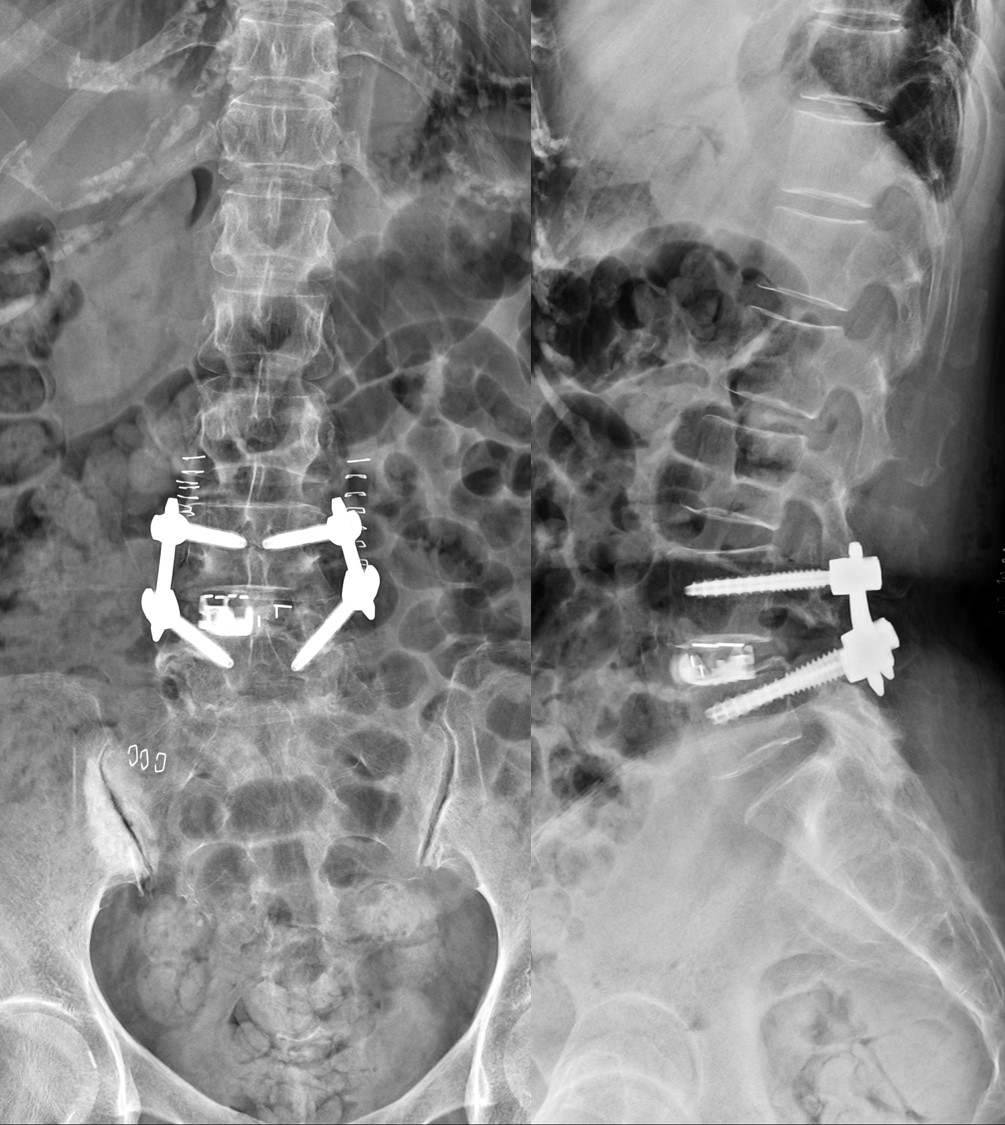

- Specialized Techniques: VGHTPE offers leading minimally invasive procedures, especially minimally invasive transforaminal lumbar interbody fusion (MIS-TLIF) and oblique lateral interbody fusion (OLIF). Both techniques allow for precise removal of damaged discs and insertion of fusion cages and screws with minimal tissue disruption.

- MIS-TLIF: Accesses the spine through small incisions in the back, providing excellent nerve decompression and secure spinal stabilization.

- OLIF: Approaches the spine from the side of the abdomen, avoiding back muscle disruption and offering advantages for complex or multi-level disease and spinal deformity.

- MIS-TLIF (Minimally Invasive Transforaminal Lumbar Interbody Fusion): Two small incisions are made in the lower back under navigation guidance. Muscles are gently separated, rather than cut. The facet joint is removed to decompress nerves and access the spine. The damaged disc is removed, and a fusion cage with bone graft is inserted. Pedicle screws and rods are placed through the same small incisions to stabilize the spine, guided by computer navigation and intraoperative imaging.

- OLIF (Oblique Lateral Interbody Fusion): A small incision is made on the side of the abdomen to access the spine, avoiding back muscle injury. The disc is removed and replaced with a specially designed cage to restore disc height and spinal alignment. Additional screws and rods may be added for stability, either in the same or a separate stage.